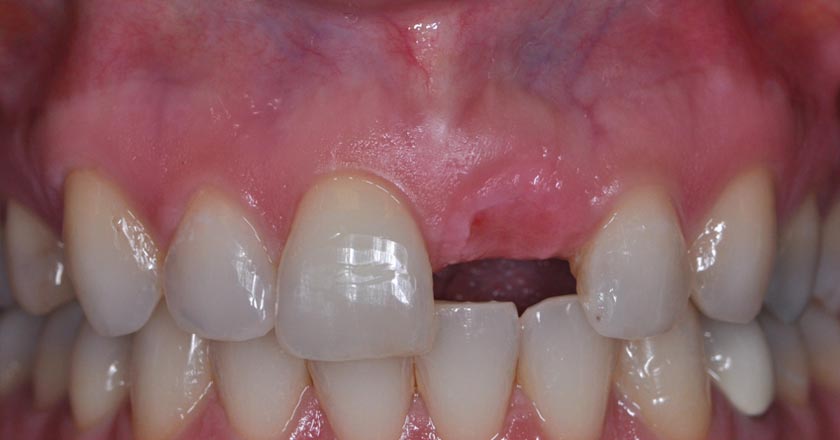

Implant - Before And After